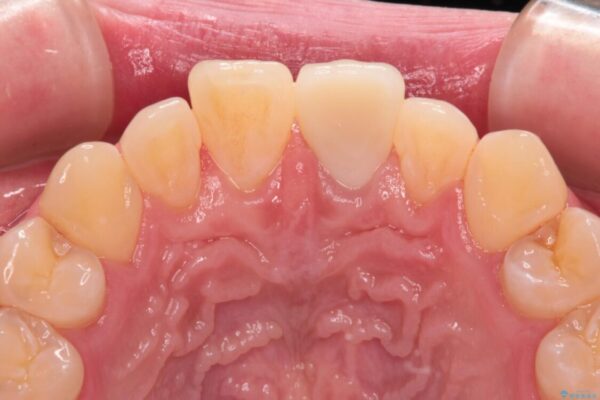

神経を取り除いたことで変色した前歯を気にして来院された患者様です。

根管治療はやり直さずに、ファイバーポストを使用した土台を植立してオールセラミッククラウンにて補綴することとしました。

治療前

• 変色した前歯をオールセラミッククラウンに 治療前画像